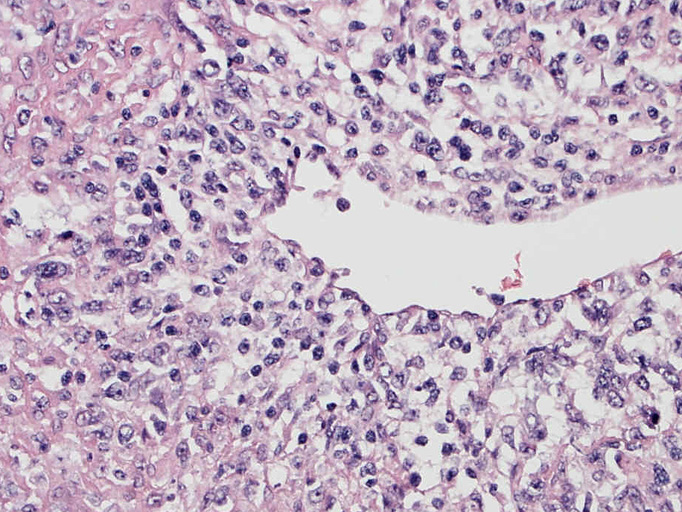

• 組織学的に,LyGは,様々な割合のリンパ球と大きなEBV+芽球からなる血管中心の浸潤を特徴としており,その中にはHRSに類似した特徴を示すものが出現する. 血管浸潤とそれに伴う多量の凝固壊死が典型的な所見である.

EBUS-GS(ガイドシース併用気管支腔内超音波断層法)による肺生検組織病理所見.

血管周囲性に大型類円形核や不整形核をもつ腫瘍細胞がシート状密に浸潤増殖している. Mitosisが多く認められる.細血管閉塞や破壊の所見がある.

間質にもシート状の腫瘍細胞浸潤がある. 大小 pleomorphicな傾向.(A, B). necrosisが認められる(C). 細気管支上皮直下まで密な浸潤あり, 小型リンパ球が混在している.(D)

血管中心性浸潤. 障害された血管内に血栓が形成されている.CD20陽性細胞がシート状密に浸潤, CD3陽性T細胞が多く混在している. EBER-ISH陽性 EBV感染細胞が多数認められ, >50 hpf, 定義より Grade3となる. 陽性細胞のサイズは大小さまざまであることに注意.